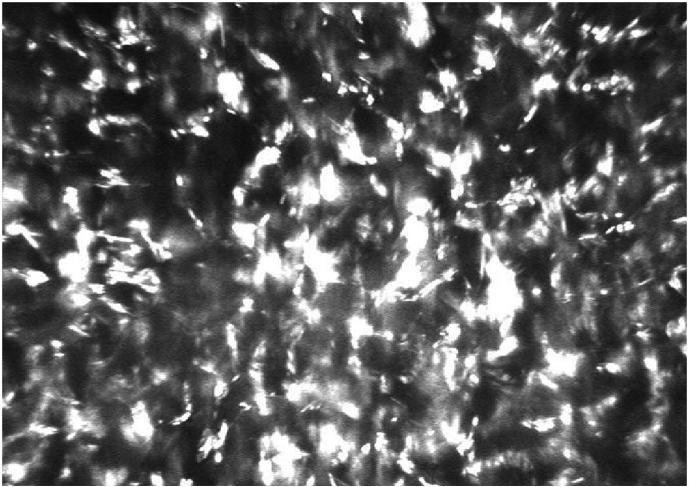

Slit-lamp examination revealed bilateral fine iridescent confluent crystalline deposits in all layers of the cornea, both peripherally and centrally. Systemic evaluation revealed abnormal M protein, IgG-kappa type, in blood and urine. Bone marrow aspiration showed a monoclonal plasma cell concentration of 2%. Consequently, the patient was diagnosed with MGUS. Because of progressive bilateral visual loss in the following 10 years, a perforating keratoplasty was performed on the left eye. Immunohistochemical analysis of the native cornea (the corneal button) revealed depositions of the same M protein type as detected in plasma and urine. Electron microscopy showed rhomboid-shaped corneal deposits of various sizes up to 4 μm. Recurrence of crystalline keratopathy was observed 9 months after keratoplasty. The monoclonal protein remained stable and the MGUS did not progress to multiple myeloma nor a related disorder.

裂隙灯检查发现角膜各层均有双侧细小的彩虹样融合结晶沉积物,周边及中央均有。全身评估显示血液和尿液中存在异常M蛋白,IgG-κ型。骨髓穿刺显示单克隆浆细胞浓度为2%。因此,该患者被诊断为MGUS。由于在接下来的10年中双眼视力逐渐丧失,对左眼进行了穿透性角膜移植术。对原角膜(角膜植片)的免疫组织化学分析显示,沉积物的M蛋白类型与血浆和尿液中检测到的相同。电子显微镜显示角膜沉积物为菱形,大小不一,最大可达4μm。角膜移植术后9个月观察到结晶性角膜病变复发。单克隆蛋白保持稳定,MGUS未进展为多发性骨髓瘤或相关疾病。